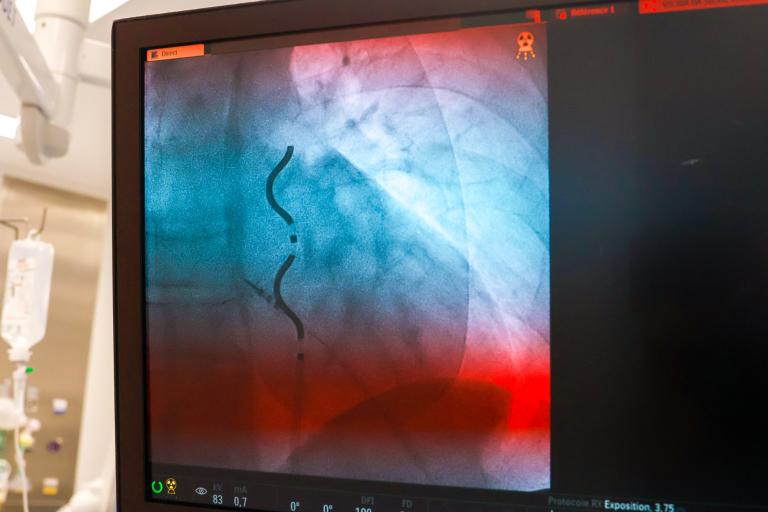

Implanté sous l’aisselle gauche (région médio-axillaire gauche), le boîtier est associé à une sonde de défibrillation positionnée sous le sternum par une approche mini-invasive. Ce positionnement extravasculaire vise à réduire les complications à long terme pouvant être associées aux sondes transveineuses, notamment l’occlusion des vaisseaux (rétrécissement ou obstruction veineuse), les fractures de sondes et le risque d’infections (endocardites infectieuses).

Le défibrillateur Aurora™ EV-ICD est implanté sous l’aisselle gauche et associé à une sonde extravasculaire Epsila EV™ MRI SureScan™, positionnée en dehors du cœur et des vaisseaux.